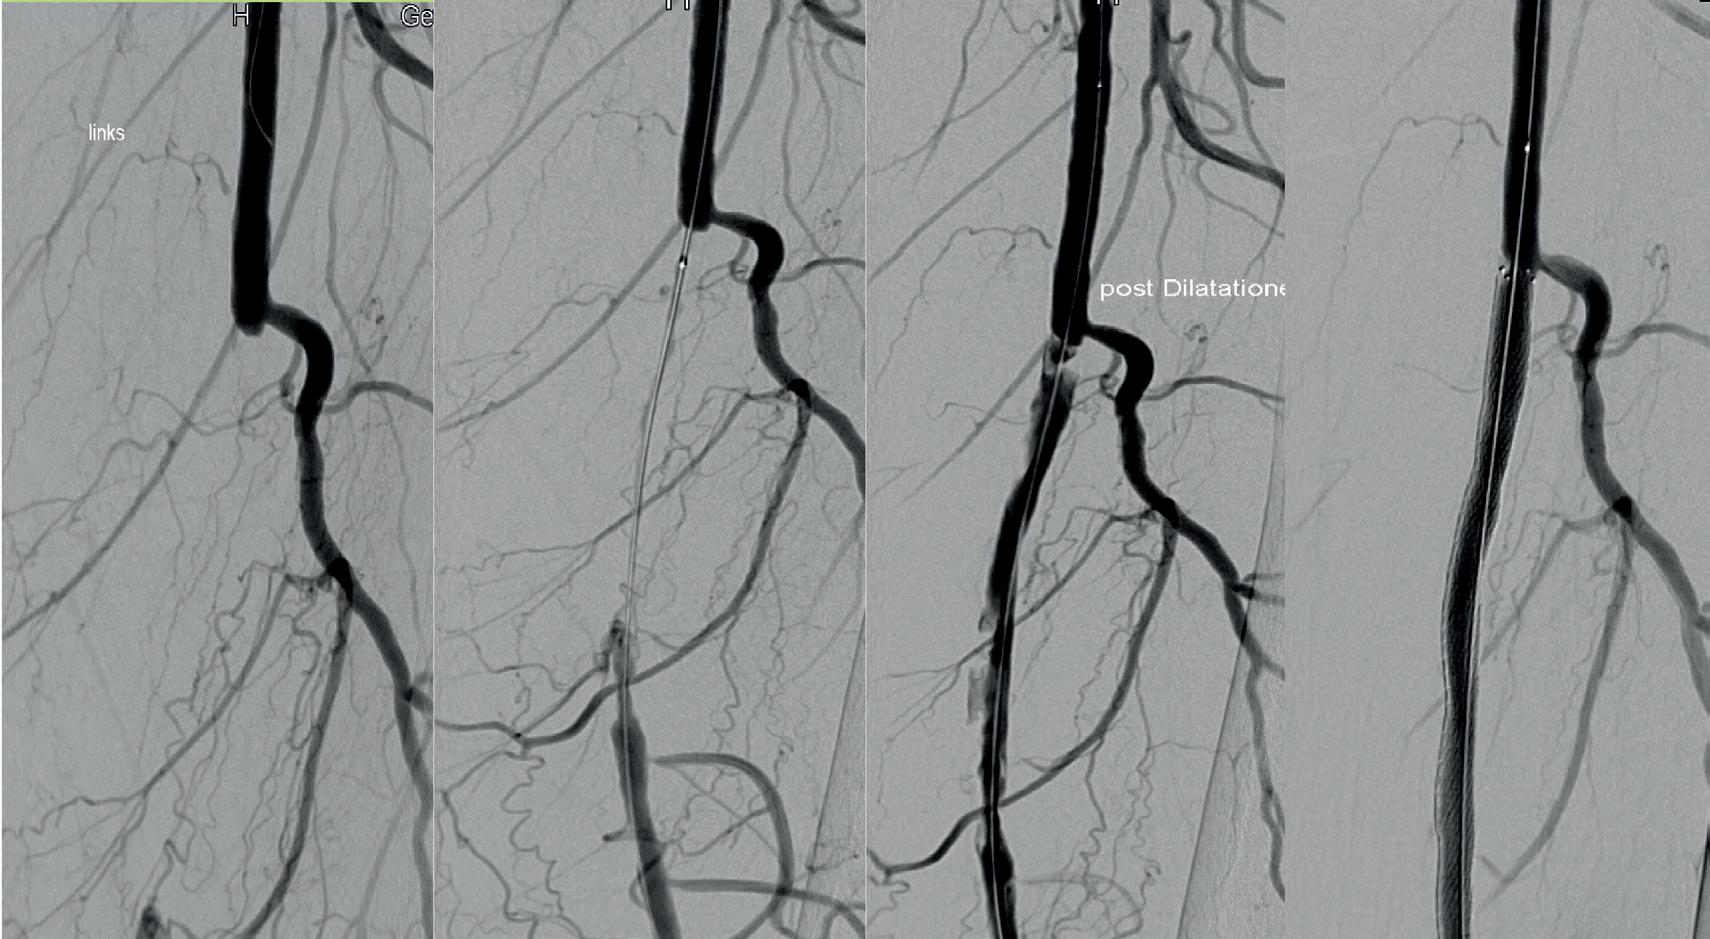

The Aperto® over-the-wire (OTW) DCB from Cardionovum—which is available in lengths of 20, 40 and 60mm and diameters from 4 up to 12mm—was developed specifically to solve unmet clinical needs in the treatment of haemodialysis access stenosis and recanalisation of arteriovenous fistula shunt grafts.

Tozzi, who is a full professor of vascular surgery at the University of Insubria, started using the Aperto in his vascular access practice over 10 years ago and is planning to soon publish his clinical experience in a study called Aperto 600.

Today, Tozzi explained, there is a pressing need for a device such as the Aperto. Haemodialysis patients now survive far longer than they used to, and therefore the key goal at present is to maintain patency of the access circuit to ensure that it can be used for several procedures over a long period of time.

“This goal has been achieved,” Tozzi reported, attributing this result to the Aperto. In his clinical practice, Tozzi shared that patients have a patent vascular access circuit without restenosis at one year after DCB treatment in the vast majority of cases.

Previously, Tozzi said, by way of comparison,

treatment being extended, with the average time in his centre now being eight months and only 6% of patients undergoing two or more procedures over the course of a year. “This is important for the patients, because it means less time in hospital,”

Tozzi commented.

treatment was limited to percutaneous transluminal angioplasty (PTA) alone, which at his centre resulted in no patients having a patent vascular access circuit at one year. The results with DCB, however, are “incredible”.

Tozzi was keen to stress that DCB is not the “final cure” for intimal hyperplasia. However, he underlined the importance of focusing on what the treatment option does offer in this regard. Significantly, he said, Aperto results in the mean time from first to second